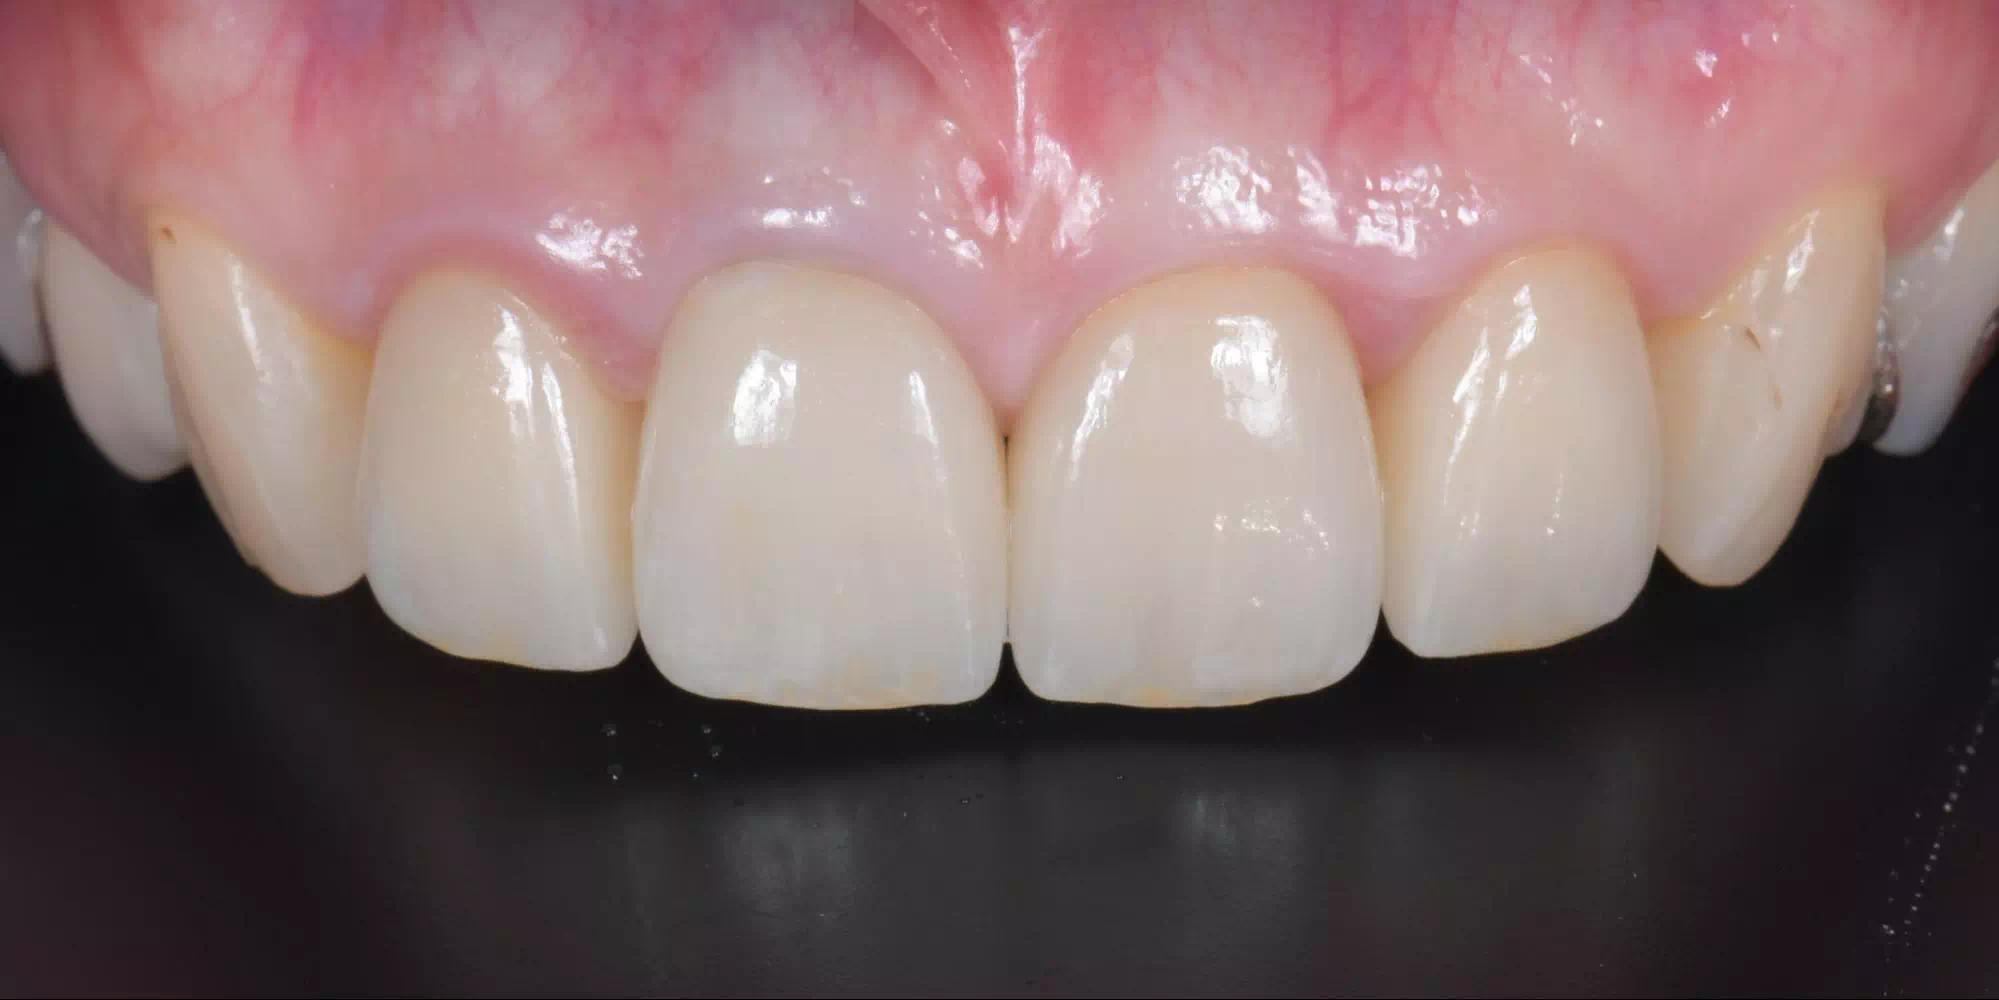

CASE HOME CASE 2025/10/21 抜歯即時埋入・即時荷重 症例 2025/10/21 GBR① 2025/10/21 インプラント 症例② 2025/10/21 インプラント 症例① 2025/10/21 矯正歯科 症例 2025/10/21 審美歯科 症例② 2025/10/21 審美歯科 症例① 2025/10/21 ガミースマイル 症例 2025/10/21 歯肉再生 症例② 2025/10/21 歯肉再生 症例① 2025/10/21 虫歯症例